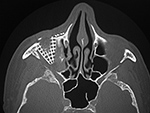

| 86 year-old man who fell off ladder onto pruning shears. The shear handle went through the floor of his right orbit and right maxillary sinus. His globe was intact. AP and lateral scout CT images. |

Axial CT image after surgical repair of the right orbital floor with titanium mesh. |

Coronal CT image after surgical repair of the right orbital floor with titanium mesh. |